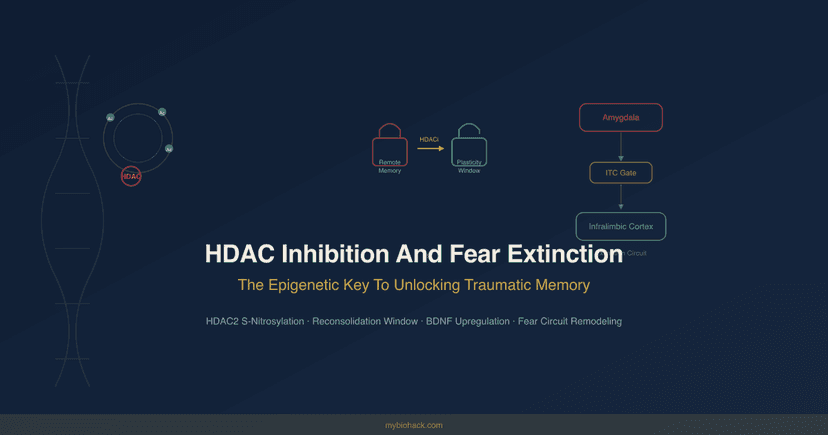

Brain Health

HDAC Inhibition And Fear Extinction: The Epigenetic Key To Unlocking Traumatic Memory

17 min read